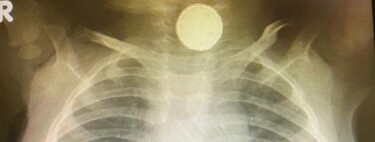

La radiografía que los médicos le hicieron a Reese en urgencias mostraba claramente la pila de botón alojada en el esófago, por lo que rápidamente decidieron intervenirla para extraérsela. Los médicos informaron a los padres de que este tipo de baterías podían causar graves secuelas, no solo porque al quedar atascadas taponan el esófago dificultando la respiración, sino porque liberan material tóxico y corrosivo que ocasiona quemaduras en los tejidos provocando lesiones devastadoras.